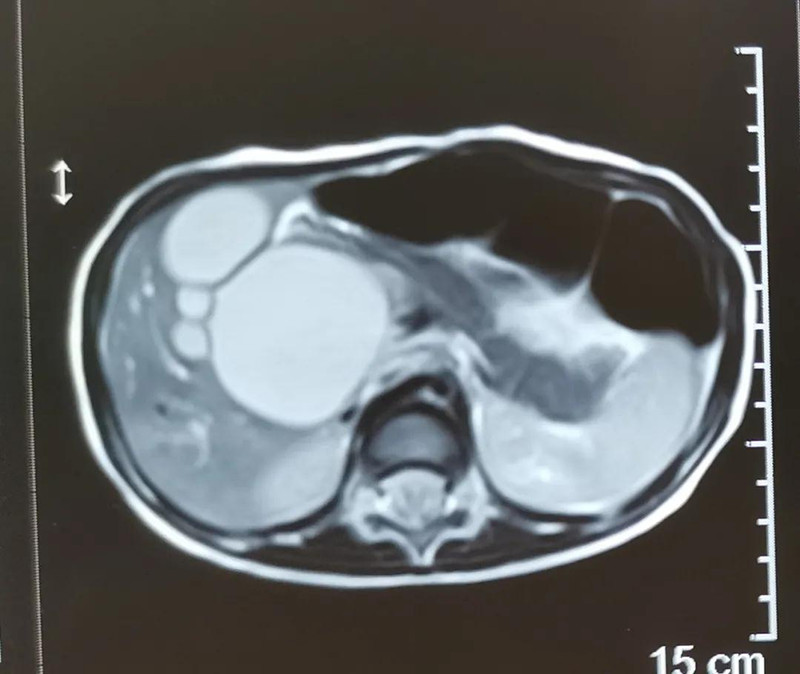

最近半个月,长春市26个月女宝馨馨(化名)脸色不好,全身发黄严重,还伴随发烧。9月23日,馨馨被家人带到德州扑克游戏网 诊治。经检查,馨馨全身发黄是因为患有黄疸,而黄疸的出现是因为胆总管发生病变,“胆总管呈现囊性扩张,下边出口被堵住,胆汁进不到肠腔里,导致孩子出现黄疸、肝功不好、白土便症状。而且胆总管胀大后,还有癌变的风险,”普外、新生儿外科主任崔钊说,馨馨需要尽快手术。为了减少损伤,崔钊主任团队制定的方案是单孔腹腔镜下胆总管囊肿根治手术。

崔钊主任说,术前大家最担心的是门静脉出血,因为它比动脉出血更凶险,可危及生命。“馨馨来院时已经出现炎症,周围粘连严重。而静脉左侧临着肝总动脉,下边连着十二指肠乳头、胰腺,它和背侧的门静脉紧贴着,一不小心,就会导致门静脉出血。”